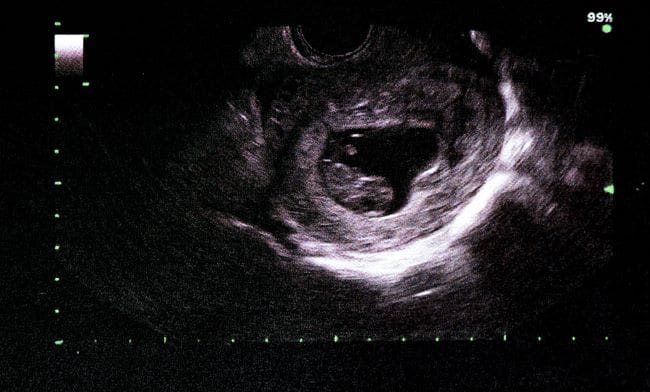

Janin 9 minggu menandakan bahwa kandungan Bumil telah berada di pertengahan trimester pertama. Pada usia kehamilan ini, ukuran janin sudah sebesar buah anggur dengan panjang sekitar 2,3 cm dan berat sekitar 27 gram. Sangat mungil ya.

Pada usia kehamilan 9 minggu, bentuk janin sudah makin menyerupai manusia nih, Bumil. Hal ini karena ekor janin sudah hilang. Tulang, sendi, serta ototnya juga sudah terbentuk. Meski begitu, tulang-tulang janin 9 minggu sayangnya belum berkembang dengan sempurna karena masih lunak.

Walau kepalanya masih berukuran besar dan dagunya belum terbentuk dengan baik, fitur wajah janin 9 minggu, seperti mata, hidung, dan mulut, juga sudah terlihat lebih jelas daripada minggu-minggu sebelumnya.

Pada usia ini, kelopak mata janin juga sudah terbentuk. Selain itu, sudah muncul sedikit pigmen warna di iris matanya meski belum bisa terlihat lewat USG 3D maupun USG 4D karena kelopak mata janin 9 minggu masih tertutup.